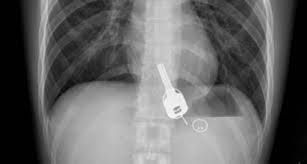

الرياض - محمد الاطلسي - قالت الصحة السعودية أن الفرق الطبية تمكنت من إنقاذ حياة مريض يبلغ من العمر 49 عاما وصل لقسم الطوارئ وهو يعاني من انسداد بمجرى التنفس، حيث اتضح بعد إجراء الفحص السريري والأشعة وجود مفتاح سيارة عالق في القصبة الهوائية.

فريق طبي بمدينة القنفذة (غرب السعودية) نجح في استخراج مفتاح سيارة عالق بالجهاز التنفسي لمريض اربعيني كاد أن يودي بحياته، في عملية سريعة استغرقت 15 دقيقة عن طريق المنظار.

اعترف للأطباء بأنه كان يلهو بالمفتاح في فمه، ابتلعه عن طريق الخطأ، مما تسبب له في حالة اختناق جزئي، تطلبت التدخل الجراحي عن طريق المنظار لاستخراج الجسم المعدني العالق. ويخضع المريض الذي اتضح أنه يعاني من أمراض في القلب بقسم التنويم لحين استقرار حالته الصحية وخروجه لإكمال فترة النقاهة بمنزله. : سعودي يبتلع مفتاح سيارته.. والسبب غريب!